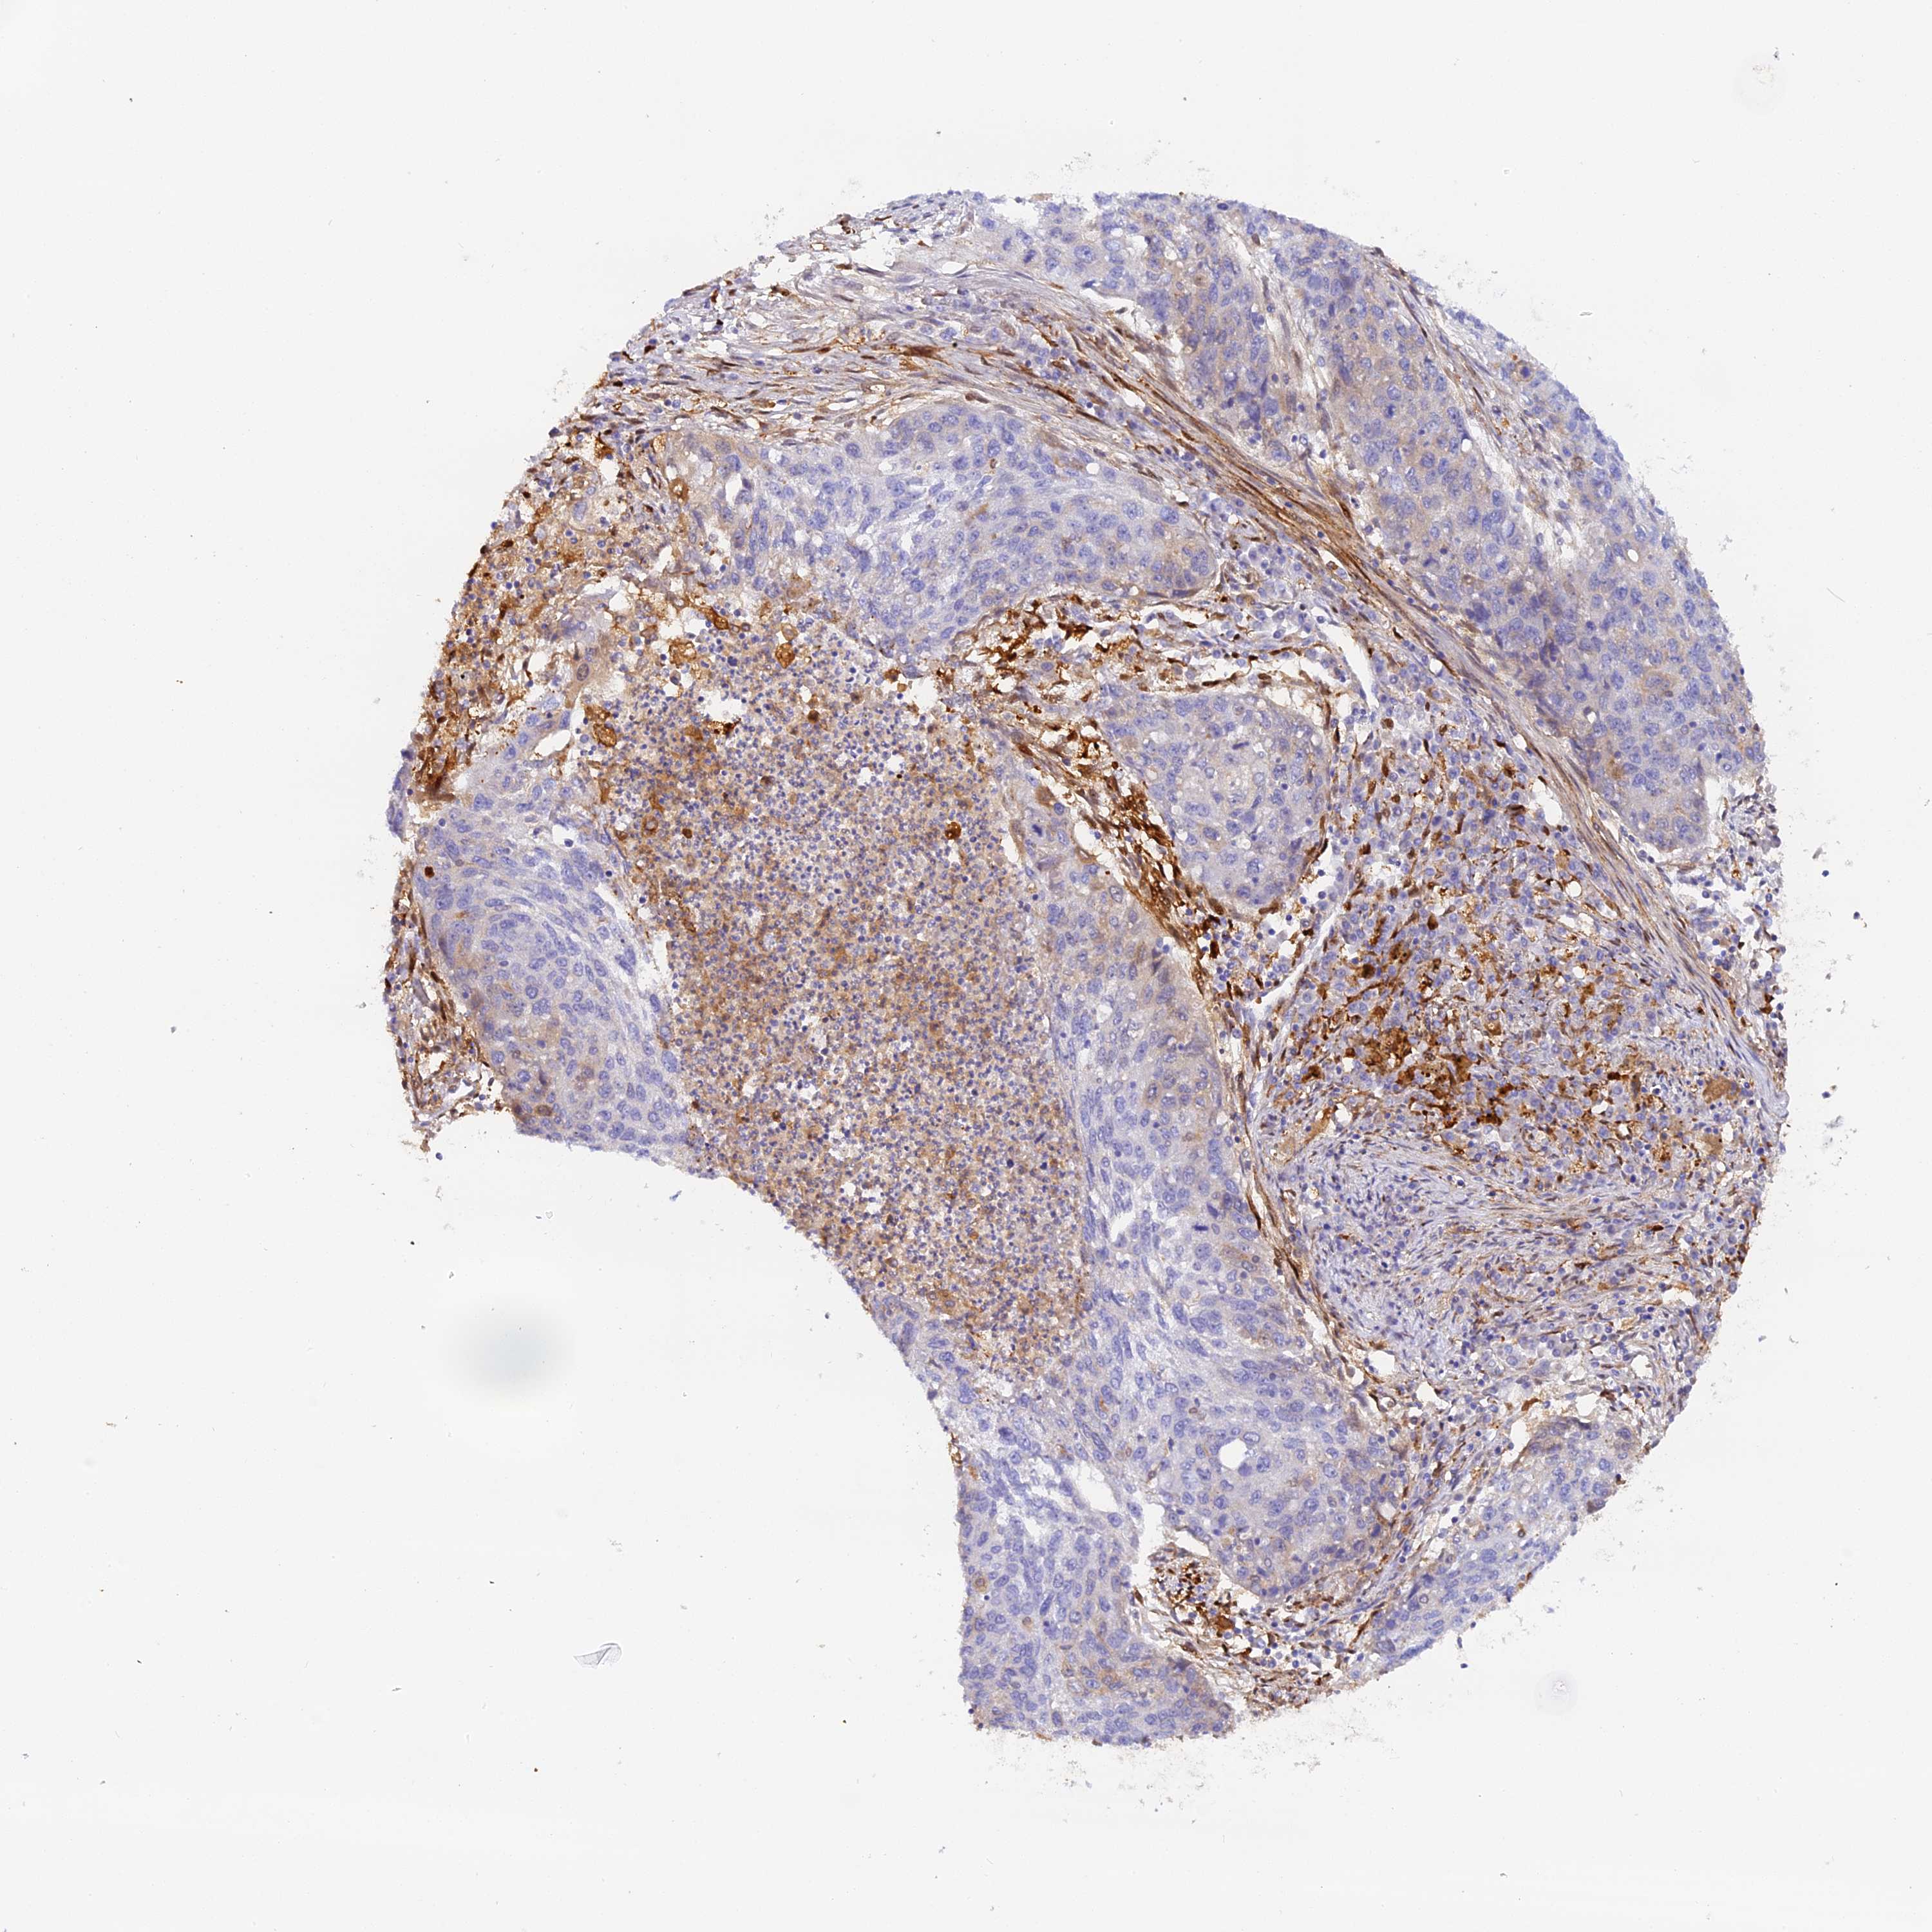

LUNG SQUAMOUS CELL CARCINOMA (TCGA) - Interactive survival scatter ploti

The Survival Scatter plot shows the clinical status (i.e. dead or alive) for all individuals in the patient cohort, based on the same data that underlies the corresponding Kaplan-Meier plots. Patients that are alive at last time for follow-up are shown in blue and patients who have died during the study are shown in red.

The x-axis shows the expression levels (FPKM) of the investigated gene in the tumor tissue at the time of diagnosis. The y-axis shows the follow-up time after diagnosis (years). Both axes are complimented with kernel density curves demonstrating the data density over the axes. The top density plot shows the expression levels (FPKM) distribution among dead (red) and alive patients (blue). The right density plot shows the data density of the survived years of dead patients with high and low expression levels respectively, stratified using the cutoff indicated by the vertical dashed line through the Survival Scatter plot. This cutoff is automatically defined based on the FPKM cutoff that minimizes the p-score. The cutoff can be changed by dragging the vertical line or by entering a cutoff value in the square labeled "Current cut-off".

Under the Survival Scatter plot the p-score landscape (black curve; left axis) is shown together with dead median separation (red curve; right axis). Dead median separation is the difference in median mRNA expression between patients who have died with high and low expression, respectively. It is calculated as follows: median FPKM expression of dead patients with high expression - median FPKM expression of dead patients with low expression. This is intended to aid the user in visually exploring custom cutoffs and the associated p-scores and dead median separation.

Individual patient data is displayed and can be filtered by clicking on one or more of the category buttons on the top of the page. Categories describing expression level and patient information include: high, low, alive, dead, female, male and tumor stages. The scale of the x-axis can be toggled between linear and log-scale by clicking on the "x log" button. Mouse-over function shows TCGA ID, patient information and mRNA expression (FPKM) for each patient.

& Survival analysisi

Kaplan-Meier plots summarize results from analysis of correlation between mRNA expression level and patient survival. Patients were divided based on level of expression into one of the two groups "low" (under cut off) or "high" (over cut off). X-axis shows time for survival (years) and y-axis shows the probability of survival, where 1.0 corresponds to 100 percent.

KATNB1 is not prognostic in Lung Squamous Cell Carcinoma (TCGA)

: 16.22

Average pTPM 20.3

Number of samples 489